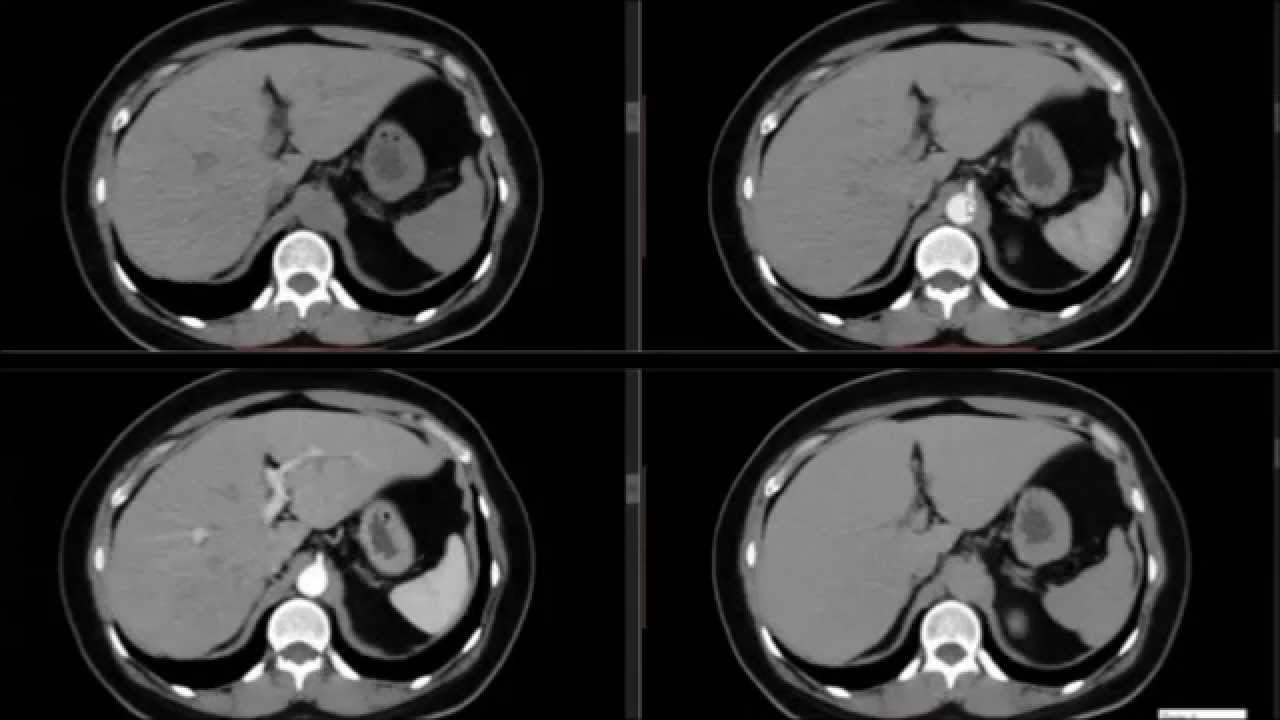

corte transversal então você consegue fazer uma reconstrução multiplanar em outros planos só que essa imagem ela não é tão boa nem nos cortes como corte frontal ou sagital né porque imagem primária e axial isso porque a aquisição é não isotrópico seja o festival será direcionado para fazer um plano transverso na mas é hoje em dia com a melhor a técnica aí da reconstrução da imagem tá bem melhor então nós temos aqui um exemplo tomografia de abdômen na imagem primária é essa imagem tá então essa imagem que o exame fornece e quando se solicita você pode

fazer uma reconstrução em outros planos né e um plano aqui frontal né ou e um plano aqui sagital também tá então a gente consegue aí mas é fazer essa reconstrução né solicitando essa o tipo de processamento da imagem e também se consegue fazer uma reconstrução tridimensional através de softwares específicos então aqui mostrando esse tipo né de softwares então é um software que consegue através da imagem já formada eu consigo manipular né então consigo ir acrescentando uma rádio densidade ou tirando o rádio da cidade então veja que eu consigo aqui manipular a bença a estrutura né